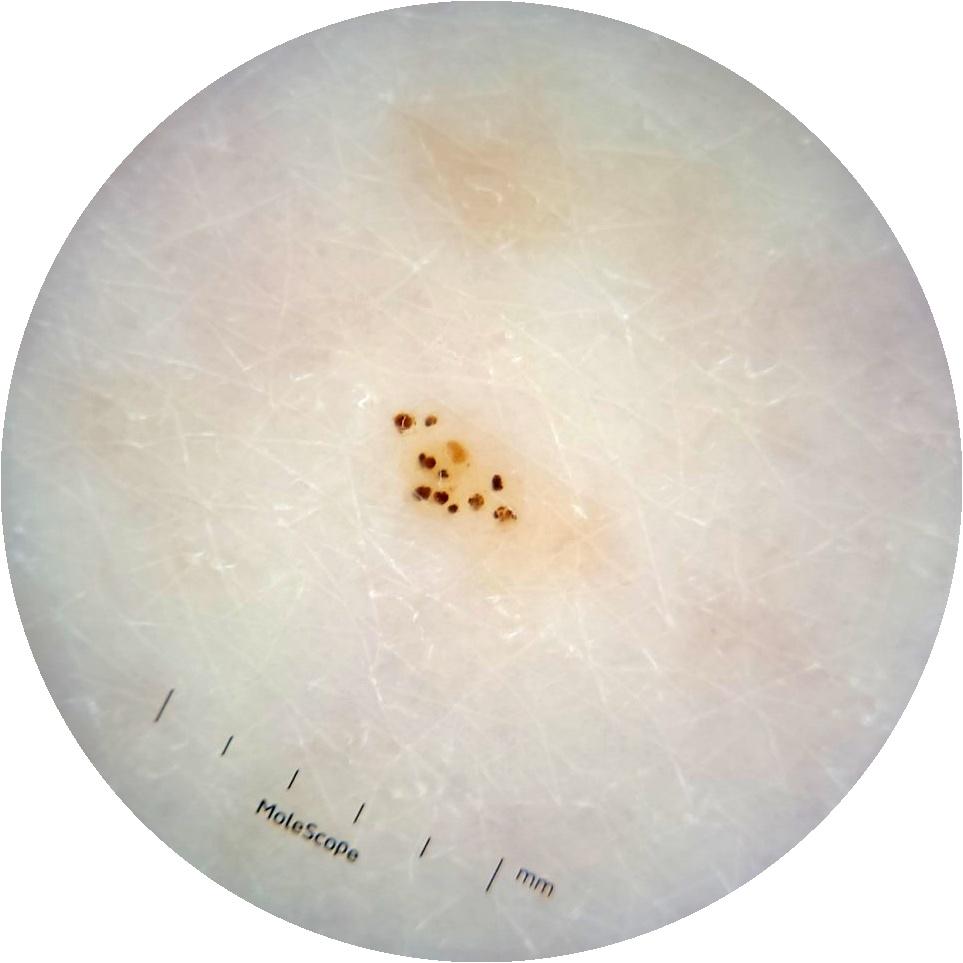

ISIC_6363669

923 x 923

acquisition_day 264

age_approx 65

anatom_site_1 Trunk

anatom_site_2 Anterior trunk

anatom_site_general anterior torso

diagnosis_1 Benign

diagnosis_confirm_type single image expert consensus

image_type dermoscopic